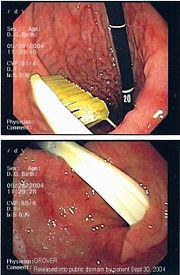

Commonly swallowed objects include coins, buttons, batteries, and small bones (such as fish bones), but can include more complex objects, such as eyeglasses, spoons, and toothbrushes (see image).

Once the foreign body has been identified with the gastroscope, various devices can be passed through the gastroscope to grasp or manipulate the foreign body. Devices used include forceps, which come in varying shapes, sizes and grips, snares, and oval loops that can be retracted from outside the gastroscope to lasso objects, as well as Roth baskets (mesh nets that can be closed to trap small objects), and magnets placed at the end of the scope or at the end of orogastric tubes. Some techniques have been described that use foley catheters to trap objects, or use two snares to orient foreign bodies.